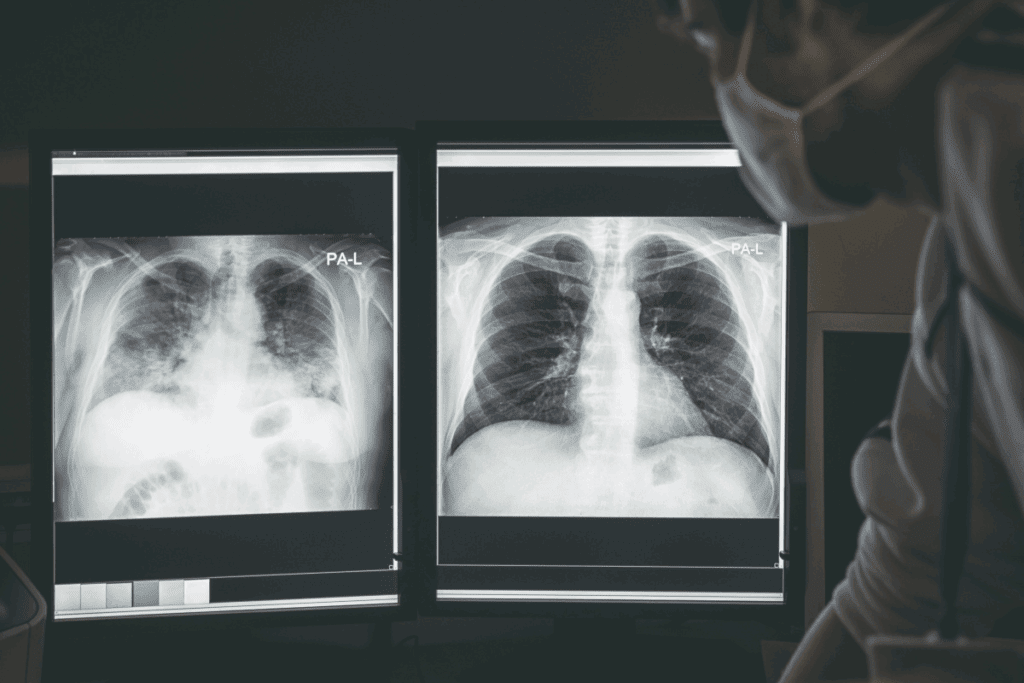

Your doctor might suggest a CT lung biopsy if they see odd lung nodules or masses on scans. This test is key for checking lung health, mainly when other tests show possible problems. A CT-guided lung biopsy helps doctors get precise tissue samples from the lungs.

Before your biopsy with ct scan, you’ll have some tests. Blood tests check your health and for bleeding disorders. We might also do imaging tests to guide the biopsy needle.

The first step is to position the patient on the CT scan table. We make sure they are comfortable and ready for the biopsy. Initial CT scans help us find the exact spot in the lung to biopsy. These images guide us on where to put the biopsy needle.